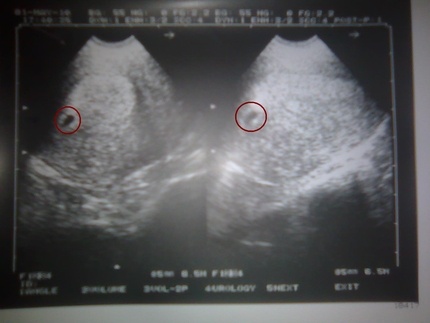

Quatre méthodes de base aideront à déterminer le nouvel état. Vous pouvez faire un test de pharmacie, faire un test sanguin pour la hCG (gonadotrophine chorionique humaine) ou subir une échographie.

Le test montrera certainement deux barres. HCG est l'une des hormones de la grossesse, donc sa teneur élevée dans le sang est une confirmation sans équivoque. Un scanner à ultrasons révélera un petit embryon. Il ressemblera à un point lumineux ou à une virgule sur un fond sombre de la cavité utérine.

C'est durant cette période que j'ai découvert qu'elle était enceinte. J'ai eu une échographie et vous savez à quel point j'étais content lorsque le médecin m'a montré ce point. C’est comme si le monde s’était renversé.